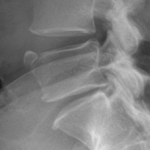

2. Limbus Bone

A limbus bone is an unfused secondary ossification center of the vertebral body (typically the anterosuperior corner), due to herniation of the nucleus pulposus through the ring apophysis prior to skeletal development. This fragment remains ununited to the vertebral body throughout the patient’s life. This can be differentiated from a fracture in that it is well-corticated, triangular, and the fragment of bone will not exactly “fit” into the defect. These fragments may be smaller than the defect of the bone (figure 2) or they may hypertrophy over time and become larger (figure 3). A limbus bone is most often asymptomatic.